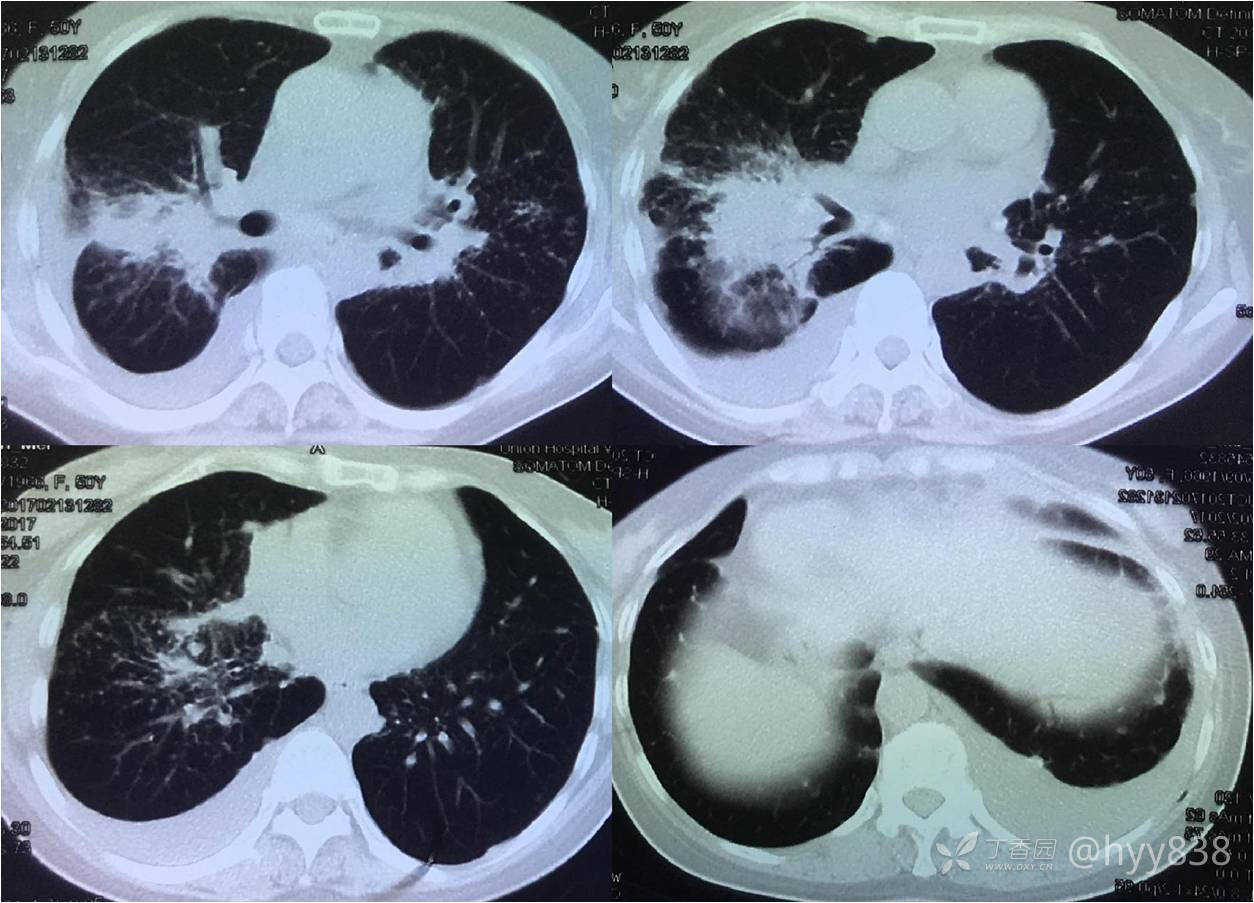

上半年抗痨治疗连续三个月复查

中间停药,下半年继续抗痨治疗

次年行CT复查,病灶进展